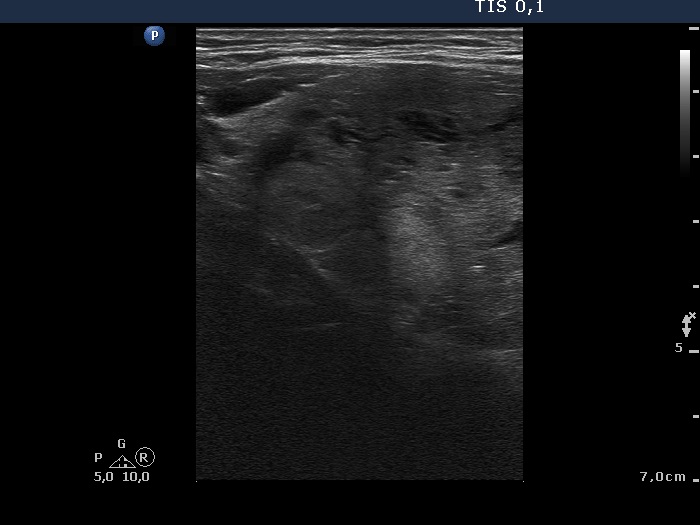

Ultrasonography. The right thyroid was composed of multiple discrete lesions with different echogenicities. The lobe was extremely enlarged with the dimension of 55x65 xminimum 120 mm (width, depth, and length, respectively) and spread retotracheal and substernal. The lower pole of the lobe could not be visualized while swallowing. The left thyroid was normal-sized and contained several hypoechogenic lesions. There was a moderately hypoechogenic nodule in the right lobe. The lesion presented neither halo nor perinodular blood flow.